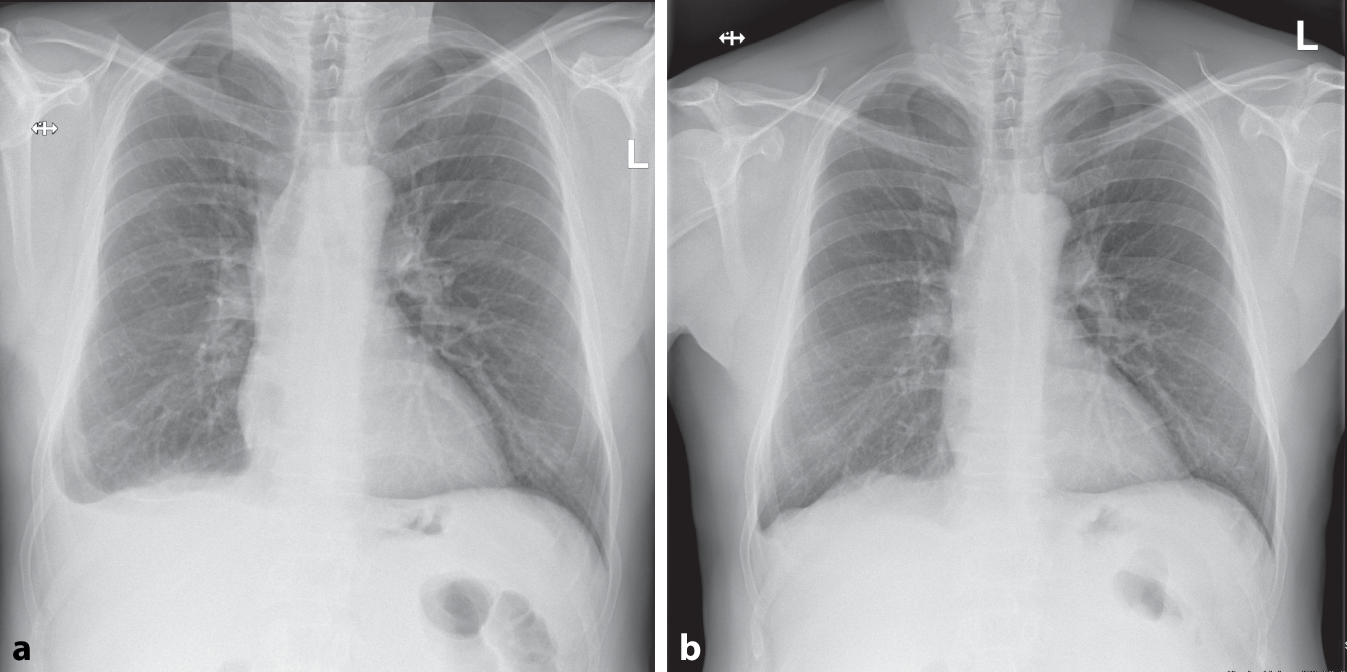

Die Therapie der Wahl ist eine 1‑malige orale Einnahme von Ivermectin 200 µg/kg Körpergewicht. Es gibt auch Mehrfachdosisregime (2 bis 4 Gaben), die 1‑malige Gabe erscheint jedoch nicht unterlegen und ist besser verträglich [5]. In der Nachkontrolle nach 4 Monaten war der Erguss nicht mehr darstellbar (Abb. 2). Eine VATS war daher nicht mehr indiziert, wäre aber ein nächster gerechtfertigter diagnostischer Schritt gewesen, wenn die Diagnose weiter unklar geblieben wäre.

Abb. 2

Vergleichende Thoraxröntgenaufnahmen vor (a) und 4 Monate nach (b) Therapie